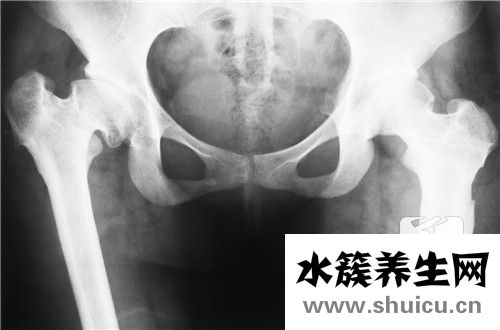

?骨盆是腰部和腿部之間的紐帶。 因?yàn)橛袃筛吒叩墓穷^,所以它看起來像一個(gè)帶有腹部的盆,因此被稱為骨盆。 在生活中,由于某些意外情況,有時(shí)骨盆也會(huì)骨折。 在醫(yī)學(xué)上,外科治療通常用于骨盆骨折。 那么,...